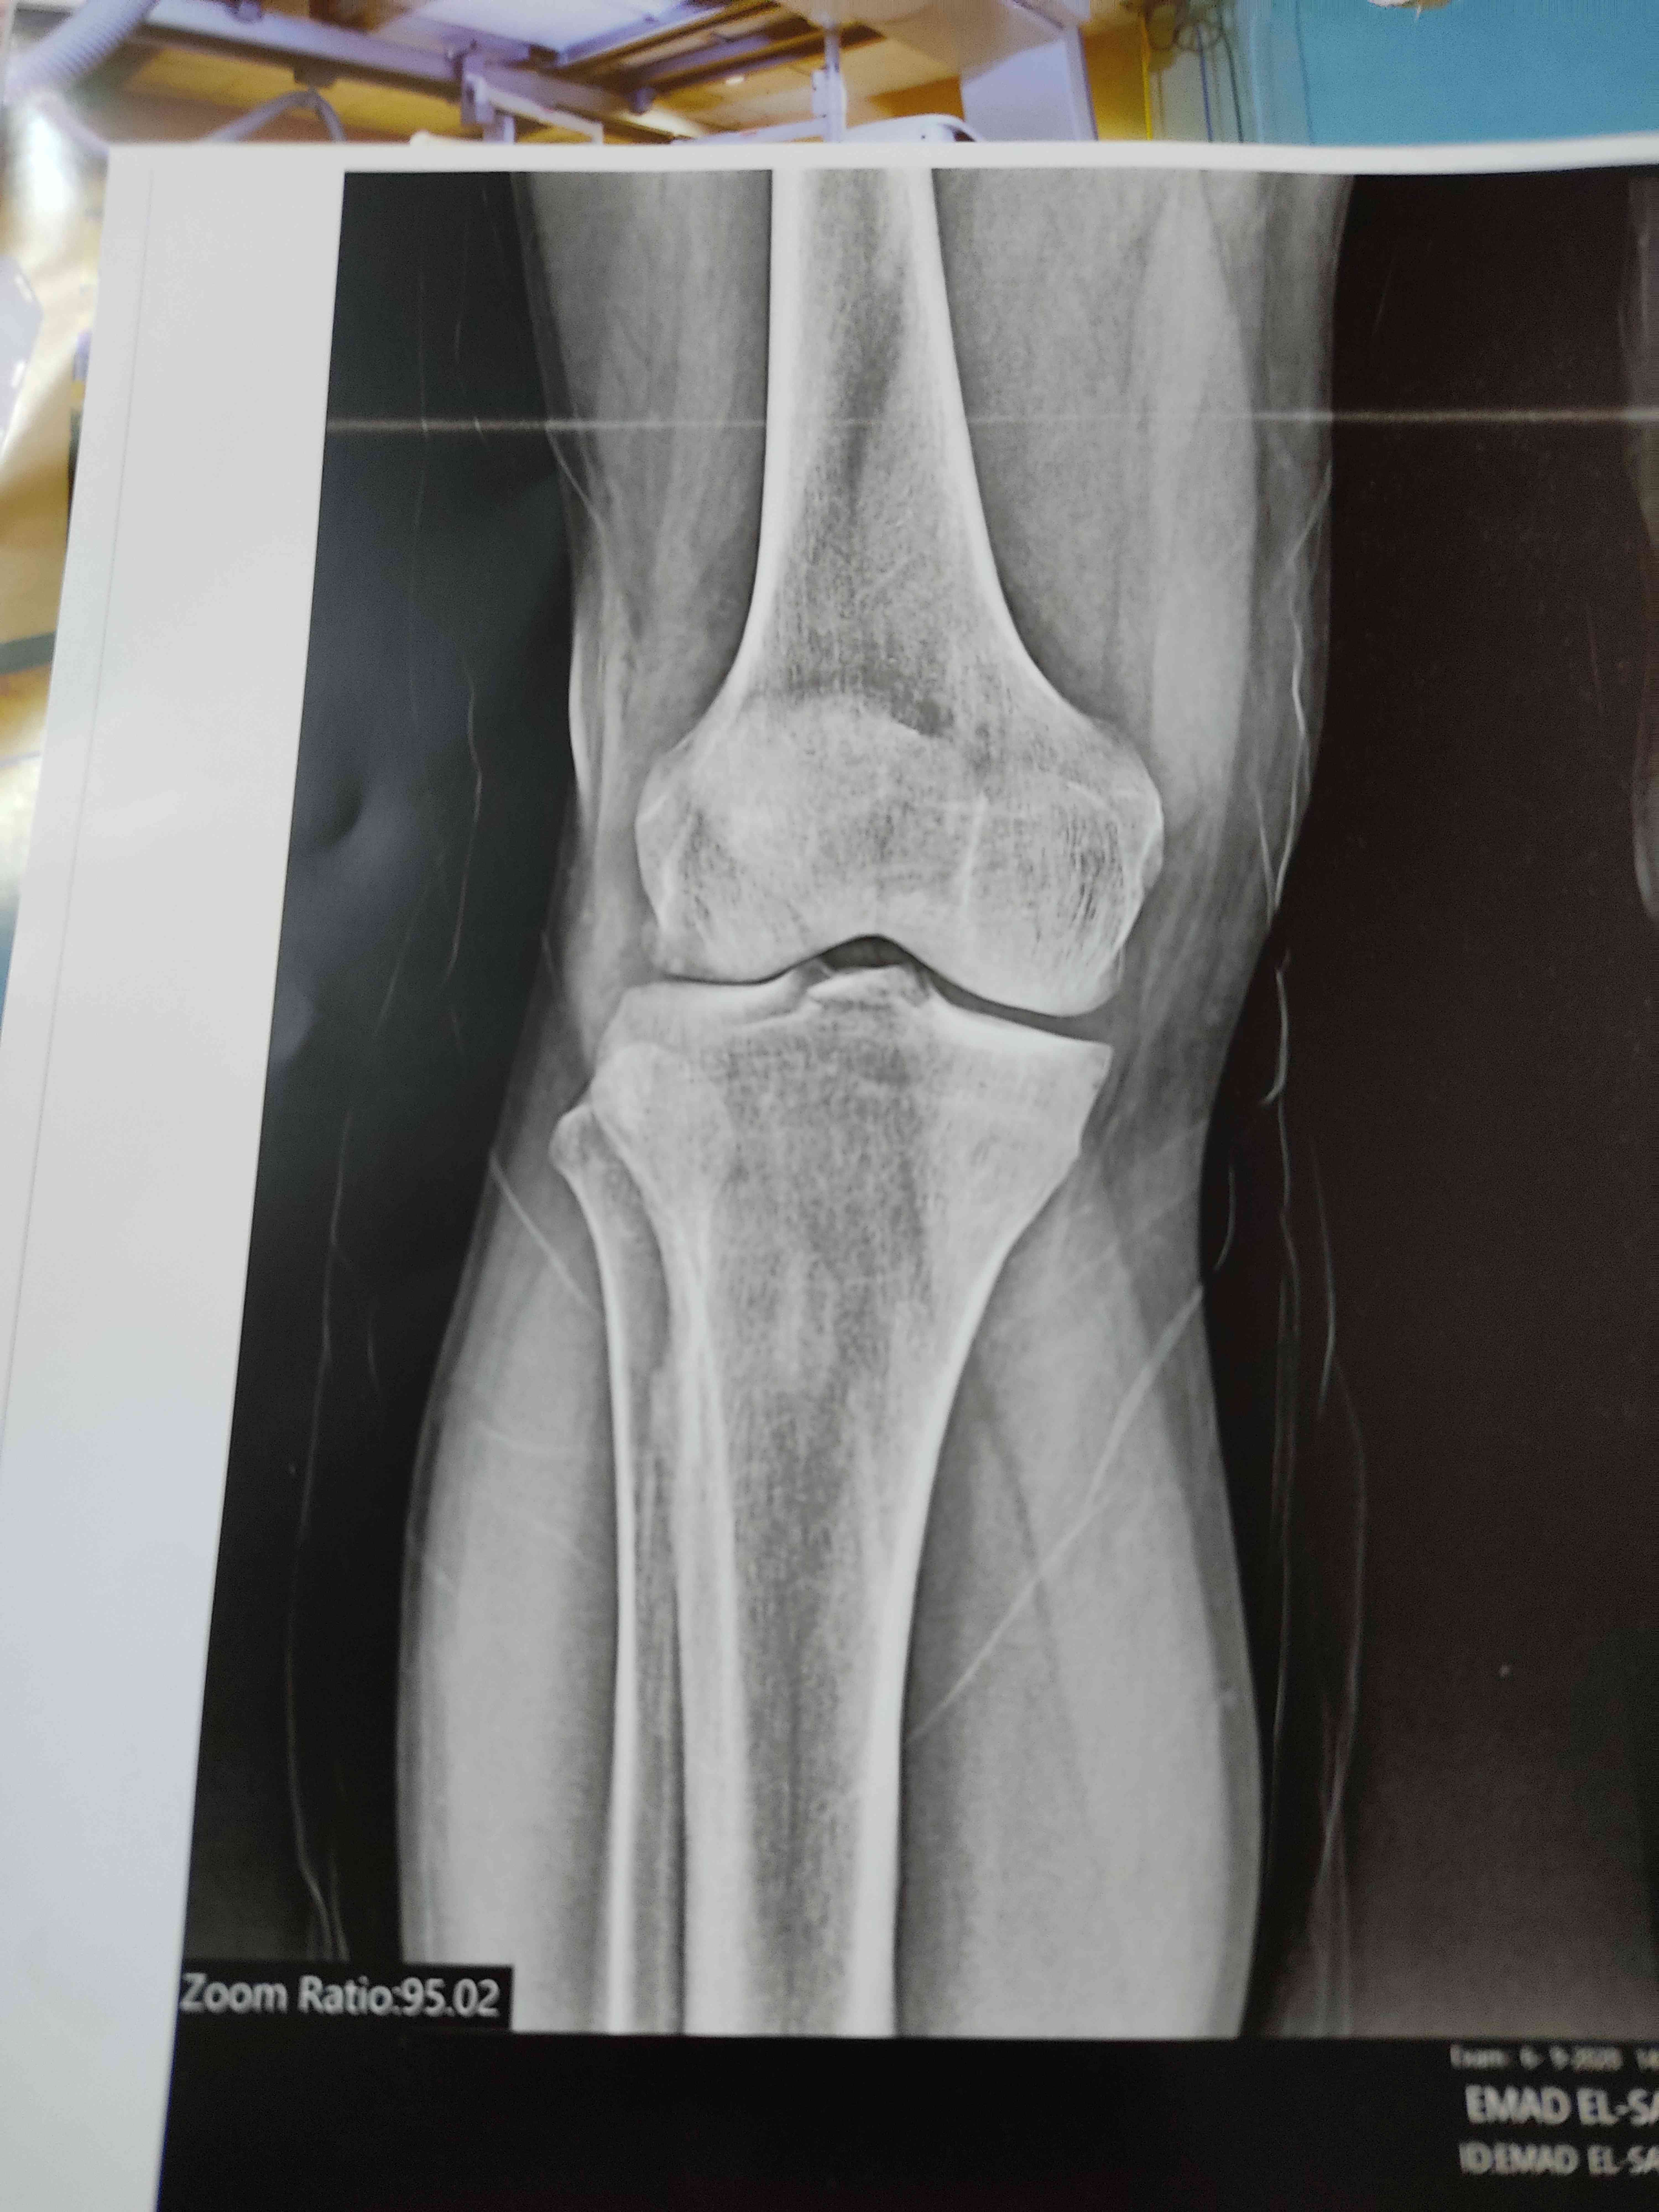

الم وغزة بالركبة نتيجة تصادم